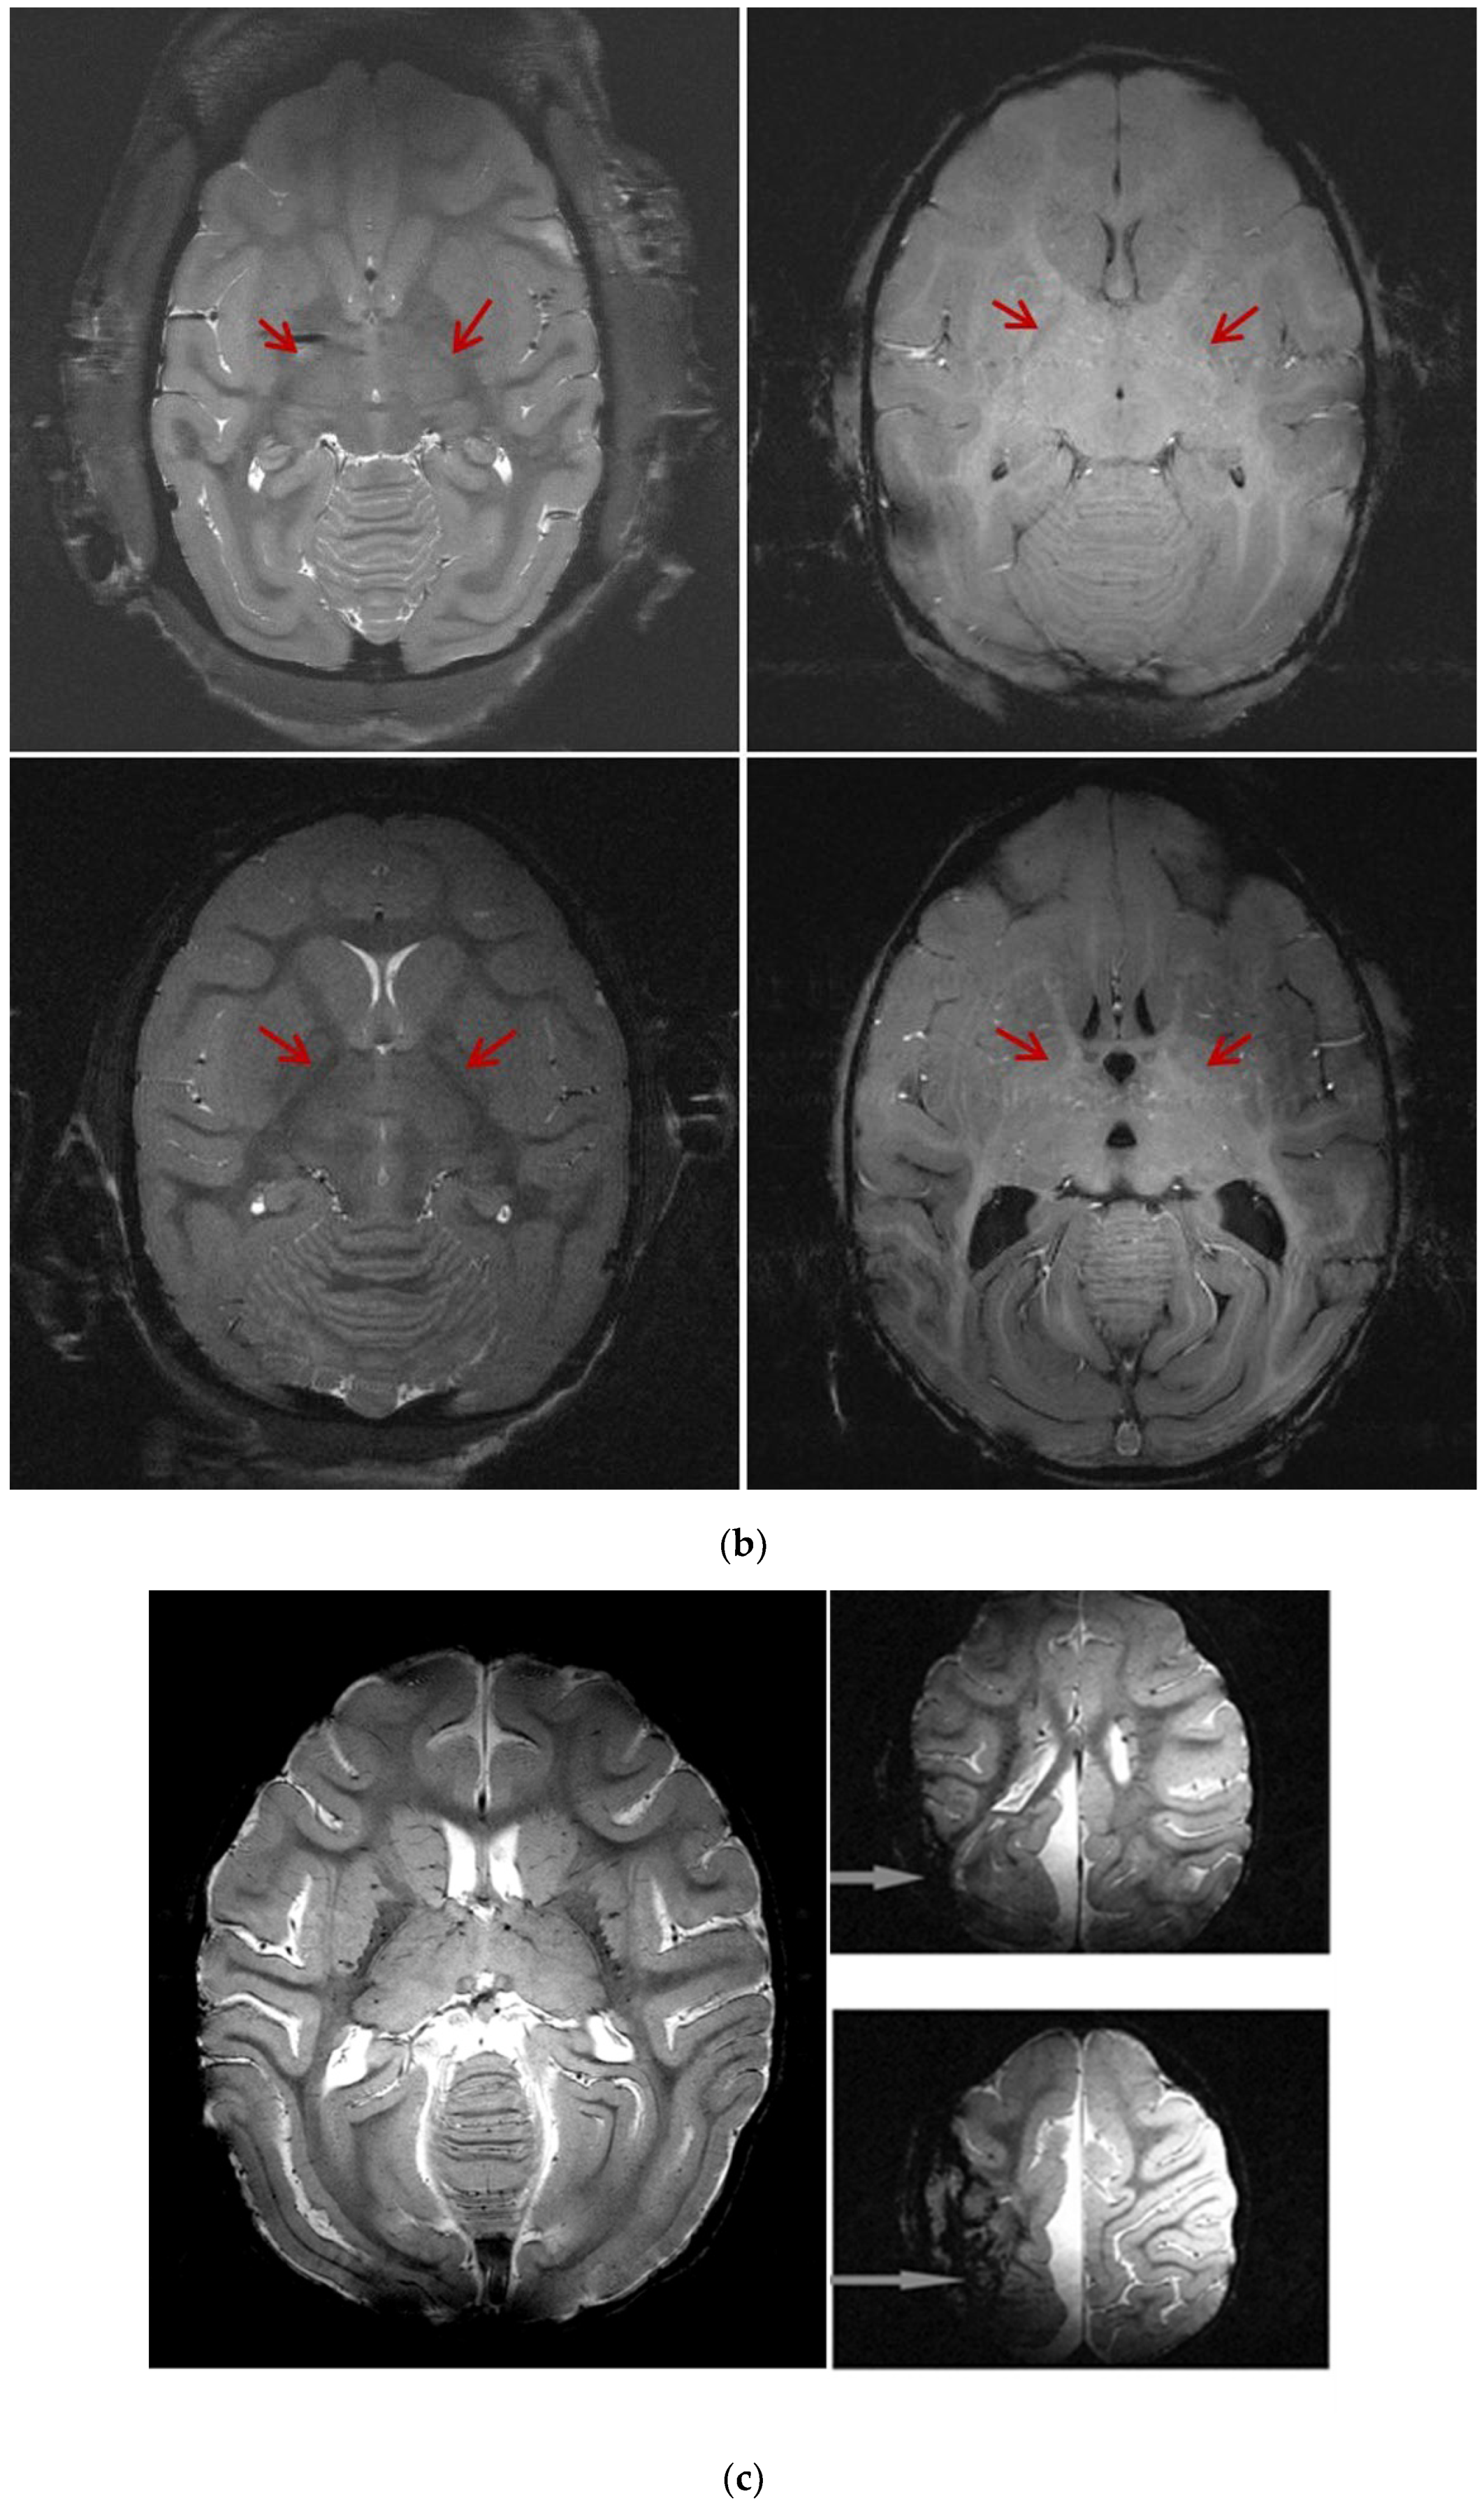

3.5. MRI